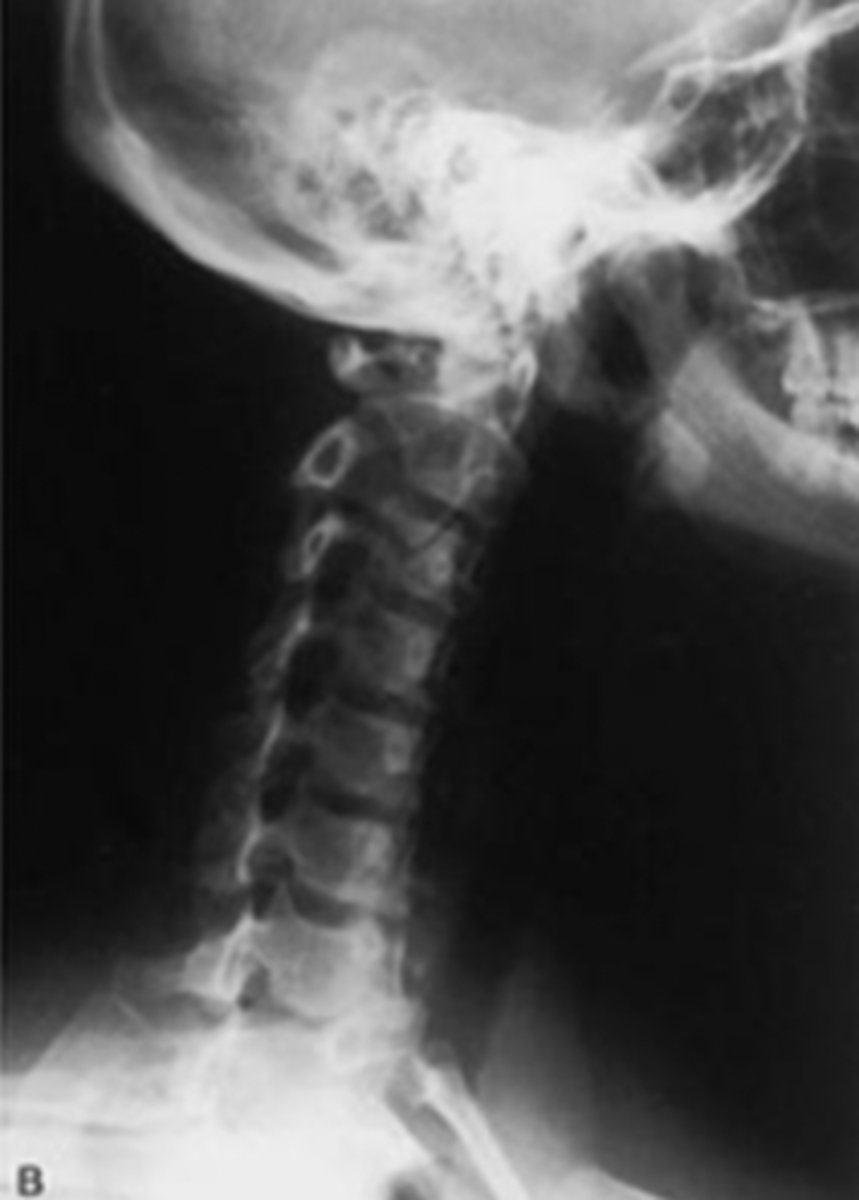

Lateral Cspine

What view is this?

What view is this? What is it great for viewing?

Lateral Csp

Best for disc space and facet joint orientation